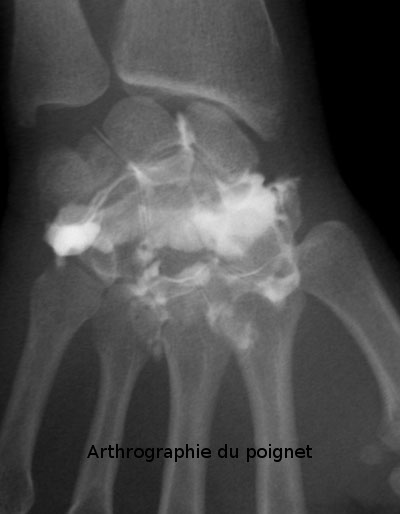

L'arthrographie est un examen radiologique consistant à introduire un produit de contraste en intra-articulaire (apparaissant en blanc sur les clichés) afin de démontrer l'intégrité ou la présence de lésions de structures intra-articulaires comme les cartilages, les ligaments, etc.

L'arthrographie est donc une technique qui utilise les rayons X et des agents de contraste qui sont en principe à base d'iode. Les articulations les plus fréquemment examinés sont l'épaule,le genou, le poignet, la hanche et la cheville.

poignet (lésion du ligament triangulaire)